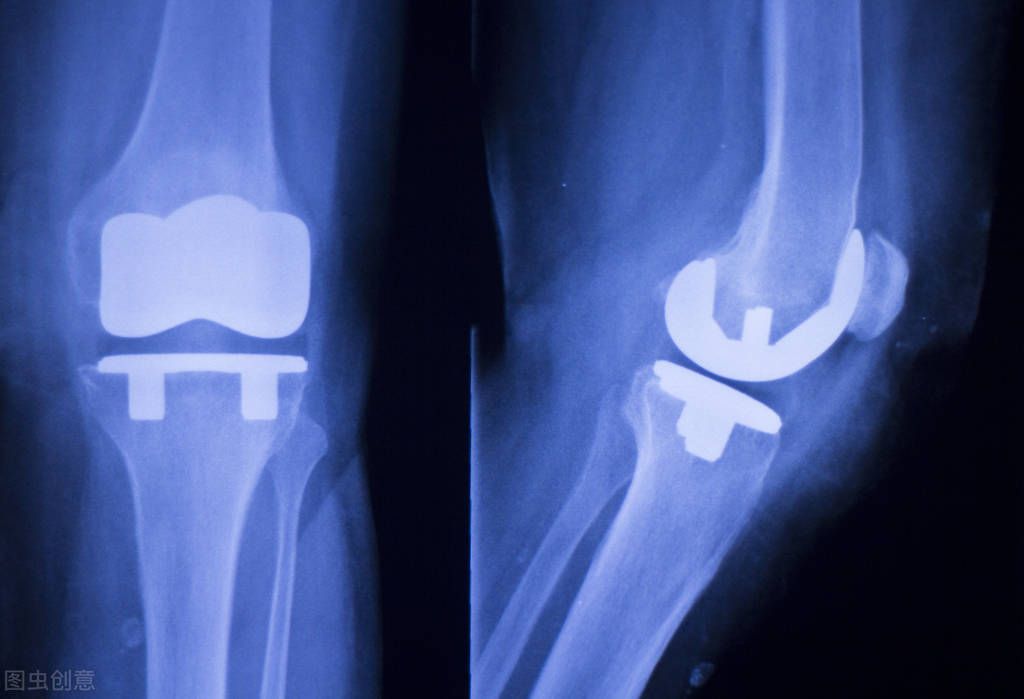

国内骨科植入物龙头,大博医疗聚焦于医用高值耗材的研产销,是业内少数的骨科植入类耗材领域全产品线覆盖的企业。涵盖创伤类、脊柱类、神经外科类、关节类、运动医学类等多种植入耗材领域,